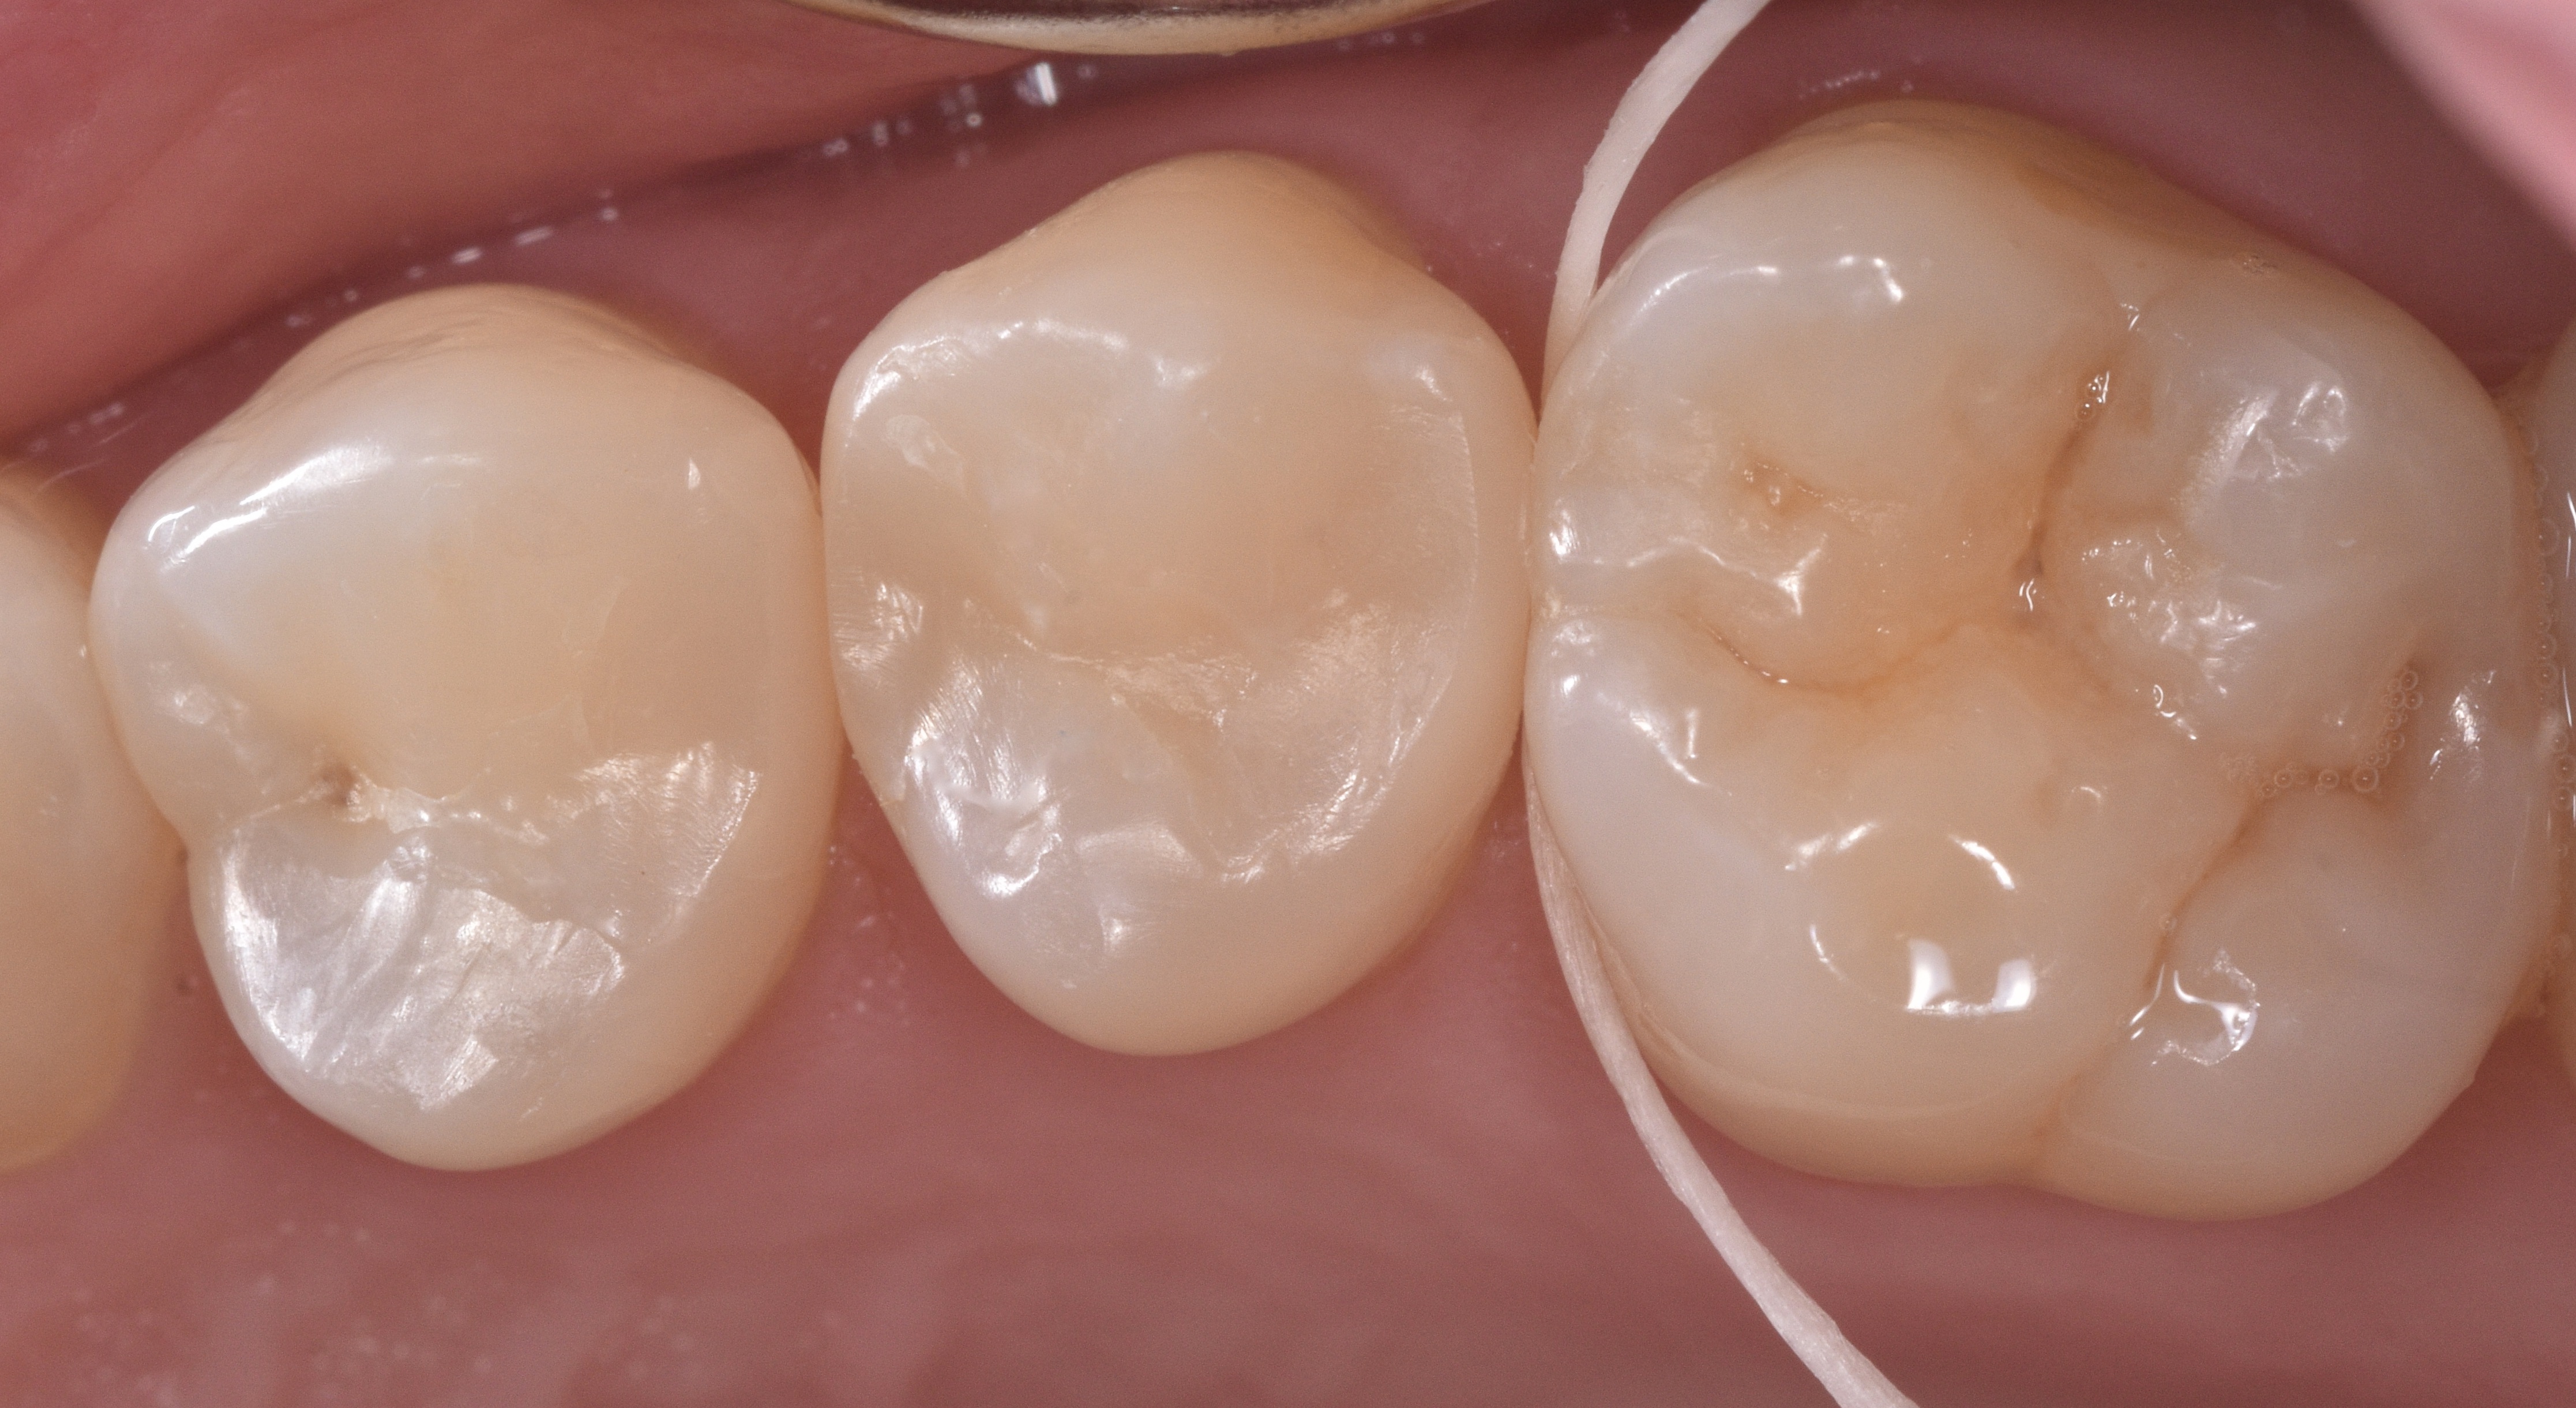

This is followed by removal of the rubber dam, adjusting occlusion, finishing and polishing using a combination of multifluted carbide burs, enhace points and soflex disc (Figure 11). Figures 12 and 13 show the fifteen days post-op follow up and the verification of ideal interproximal contact tightness.

Figure 12

Figure 13

Figure 11Figures 12 & 13